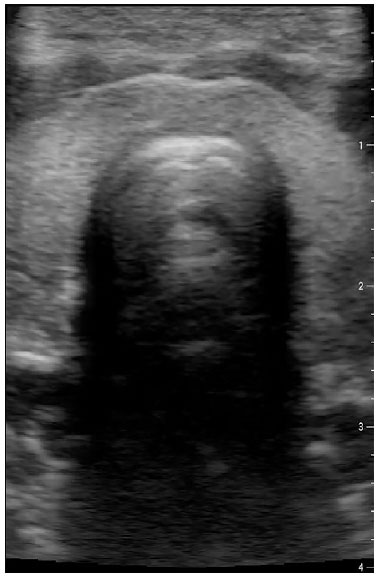

A imagem única da interface ar-mucosa, correspondendo a traqueia, deve ser visualizada para confirmar que não há tubo posicionado no esôfago do paciente. Esse artefato de reverberação posterior da imagem traqueal é também chamado de rabo de cometa, como mostra a Figura 1. Caso haja intubação esofágica, o canal anteriormente fechado (Figura 2), passa a estar aberto com o tubo em seu interior, onde visualizamos dois artefatos de rabo de cometa, com duas interfaces ar-mucosa com sombra posterior, visualizado na posição póstero-lateral a traqueia, como mostra a Figura 3.